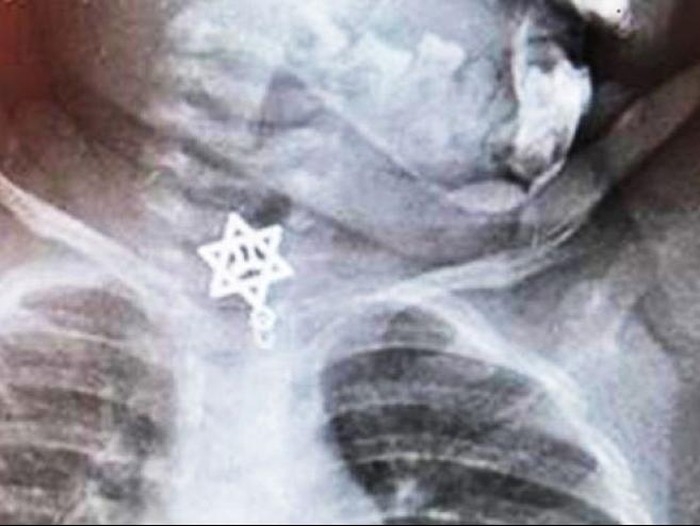

dr Udio Katzanel, dokter di Unit Gawat Darurat Pediatri di Kaplan Hospital, Rehovot, Israel Barat mengaku langsung curiga ketika diberi tahu batuk Talia tak kunjung reda. Apalagi Talia mengaku menelan sesuatu. dr Katzanel pun segera melakukan pemeriksaan x-ray.

Selama proses operasi, dr Katzanel dan tim menggunakan bantuan alat endoskopi untuk memonitor kondisi tenggorokan Talia. Akhirnya, tim bedah menggunakan teknik klem mikro-bedah untuk mengangkat liontin tersebut. Beruntung, liontin yang tersangkut itu tidak menyebabkan kerusakan pada tenggorokokam maupun organ di sekitar tenggorokan.